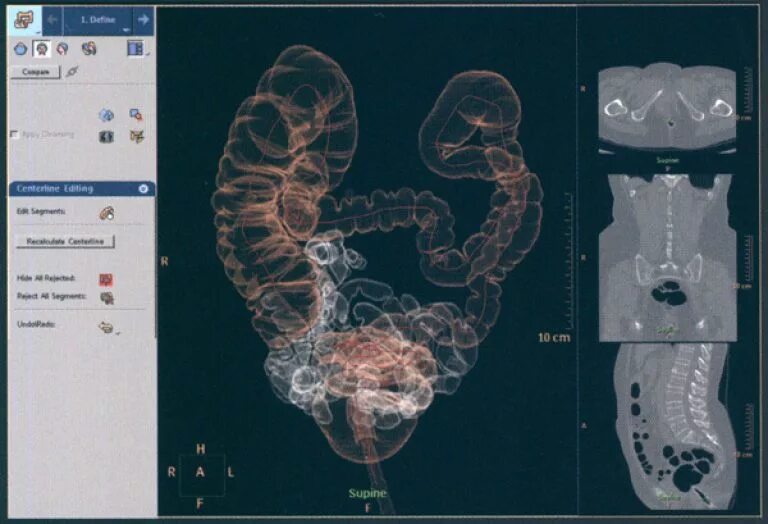

Обследование кт кишечника